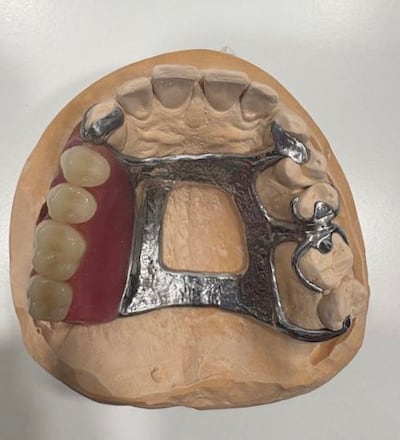

Doctors at Medcare Dentofaces in Dubai suggested a removable maxillofacial prosthesis as a viable option, as a 3D-printed device custom-made for Mr Altaher would fit perfectly inside what was left of his existing jaw.

Specialist scanners created a digital image of his mouth and then used that information with a 3D printer to create an artificial jaw that would fit perfectly inside his mouth. He has been using the fitting since August.

The device, made from metal and acrylic, can be taken out to be cleaned and simulates the lost teeth and tissue around his jaw and mouth.

They used advanced digital imaging, precision 3D modelling, and custom casting technologies to craft and fit the removable partial denture.

Not only was this designed to restore vital oral functions, but it also served to reshape Mr Altaher’s face and rebuild his confidence.